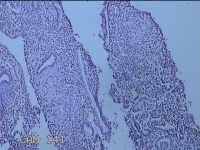

宫腔内容物

性别

女

年龄

47岁

临床诊断

1.异常子宫出血 2.慢性宫颈炎

一般病史

不规则阴道流血21天。

标本名称

大体所见

灰白暗红色不规则碎组织2.5x1.8x0.3cm一堆。

图2